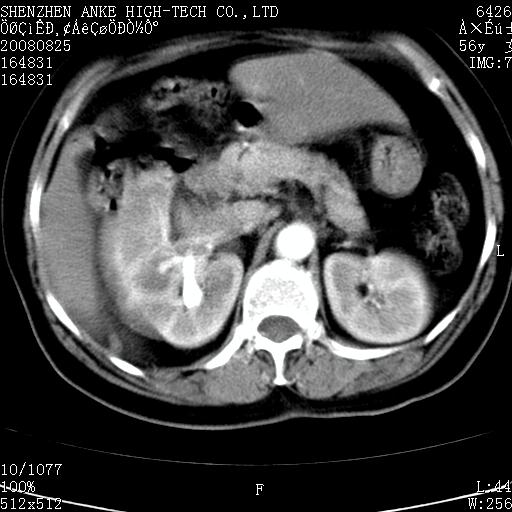

患者,女性,56岁,腰痛3年,查:右腹部约8x10cm肿块,固定,无压痛;8月23日在外院做了平扫,发现右肾巨大肿块(外院具体诊断不祥);今天在我院做了静脉肾盂造影,示:右肾明显增大,分泌功能明显减弱。

1)考虑右肾癌并右肾静脉瘤栓形成。2)脂肪肝。